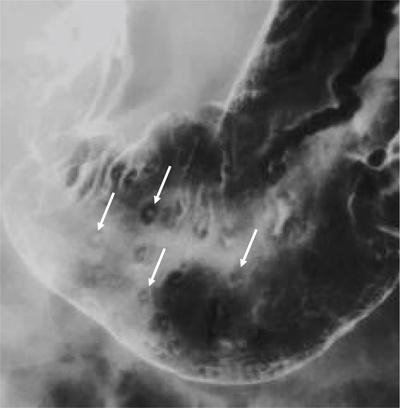

Swarup Nellore, Soumil Vyas, Ujwal Bhure, Ankit Jain, Richa Kothari, Daksh Mehta, Divya Kantesaria, Disha Lokhandwala, Karthik Ganesan The stomach is the most dilated portion of the gastrointestinal tract positioned between the oesophagus and the small intestine occupying the epigastrium, left hypochondrium and umbilical regions of the abdomen performing a multitude of functions including storage and mixing of food and controlling the passage of food into the intestine. Anatomically, the stomach is divided into the following parts (Fig. 8.2.1): the gastric cardia is the portion immediately adjoining the oesophageal opening into the stomach. The fundus is the dome-shaped part above the horizontal plane of the cardiac orifice which undergoes receptive relaxation and is the site of the autonomic pacemaker. The body is the largest part of the stomach extending from the cardiac orifice to the level of incisura angularis (notch like bend in the mid lesser curvature) containing majority of parietal cells (which secrete hydrochloric acid), chief cells (pepsinogen) and enterochromaffin-like cells (ECL). The pylorus is the tubular distal portion of the stomach which is further divided into the gastric antrum and pyloric canal. The pyloric antrum containing G-cells producing gastrin extends from the incisura angularis up to the pyloric sphincter which is an anatomical sphincter formed by concentric thickening of the circular muscle coat and encircles the narrow-slit like pyloric canal. The left dome of diaphragm and oesophagus lie superior to the stomach while the greater omentum and pancreas lie inferiorly. Spleen and liver lie on either side laterally while the transverse mesocolon is located inferolaterally. Diaphragm, greater omentum, left lobe of liver and anterior abdominal wall are anteriorly related to the stomach and contents of lesser sac including pancreas, spleen, splenic artery, transverse mesocolon, left kidney and adrenal gland lie posteriorly. The stomach is embryologically derived from the primitive foregut and is suspended anteriorly by the ventral mesogastrium and posteriorly by the dorsal mesogastrium. During development as the stomach rotates, the peritoneum grows and condenses to form perigastric ligaments, which contain blood vessels, lymphatics, lymph nodes, nerves and fat. The liver forms in the ventral mesogastrium, which develops into the falciform ligament, gastrohepatic ligament (GHL) and hepatoduodenal ligament (HDL). The spleen and pancreas form within the dorsal mesogastrium, which fuses with the posterior abdominal wall to form the gastrocolic ligament (GCL), gastrosplenic ligament (GSL) and splenorenal ligament (SRL). The perigastric ligaments are identified anatomically by the vessels contained in them (Fig. 8.2.2). The gastric cardia and lesser curvature of the stomach are attached to the inferior surface of liver by the lesser omentum by the gastrohepatic ligament respectively which contains the left and right gastric vessels. The inferior free edge of the gastrohepatic ligament extends inferiorly as the hepatoduodenal ligament between the porta hepatis and proximal duodenum gastrophrenic ligament extends between the stomach and the left hemidiaphragm. The gastrocolic ligament identified by the left and right gastroepiploic vessels, connects the greater curvature of the stomach to the anterior surface of the transverse colon. This ligament extends inferiorly as the greater omentum which is a double-layered peritoneum forming a drape anterior to the bowel loops. The gastrosplenic/lienogastric ligament bridges the posterolateral wall of the fundus and greater curvature along the proximal body of the stomach to the splenic hilum and contains the short gastric vessels. The gastrosplenic ligament is contiguous with the lienorenal ligament and both these structures constitute the lateral boundary of the lesser sac. Macroscopically the stomach shows a thick vascular mucosal lining in the form of longitudinal folds called gastric rugae. Microscopic layers of the stomach include mucosa, submucosa, muscularis externa and serosa. The mucosa includes surface mucus cells with simple columnar epithelium, gastric pits, gastric glands, lamina propria and muscularis mucosa. Submucosa includes connective tissue with submucosal Meissner’s plexus. Muscularis externa comprises three smooth muscle layers (longitudinal, circular and oblique) and Auerbach myenteric plexus. The outermost layer called serosa consists of loose connective tissue and visceral peritoneal lining. The arterial supply of stomach is constituted by the branches of celiac artery predominantly in the form of two anastomotic arcades along the lesser and greater curvature. Left gastric artery, a direct branch of the celiac trunk supplies the upper part of the lesser curvature while the lower part is supplied by the right gastric branch of the common hepatic artery arising at the upper border of pylorus. The left gastroepiploic artery, a branch of splenic artery, supplies the upper part of greater curvature and the inferior portion is supplied by the right gastroepiploic artery which is a branch of the gastroduodenal artery. The fundus additionally receives few small short gastric branches from the splenic artery. The veins follow the arteries in their nomenclature. Left and right gastric vein show direct drainage into the portal vein. The splenic vein derives flow from the short gastric and left gastroepiploic vein whereas the right gastroepiploic vein drains into the superior mesenteric vein. Pylorus can be surgically delineated by the prepyloric vein of Mayo lying on its anterior surface. Intrinsic nerve supply consists of the myenteric plexus of Auerbach and submucosal plexus of Meissner. Extrinsic nerve supply consists of sympathetic and parasympathetic components. Sympathetic nerve supply arises from T5 to T9 spinal cord segments supplying the celiac plexus via the greater splanchnic nerve. The plexuses then travel along the respective branches of celiac artery supplying the stomach. Parasympathetic nerve supply is derived from oesophageal plexus of vagus dividing into two vagal trunks. Right (posterior) vagus gives off the posterior gastric branch also called the criminal nerve of Grassi supplying the cardia and fundus of stomach. Right vagus then gives off a celiac branch and continues along lesser curvature of stomach as the posterior gastric nerve of Latarjet supplying the antrum, body and pylorus. Left (anterior) vagus gives off a hepatic branch then continues along the lesser curvature as the anterior nerve of Latarjet supplying the antrum, body and pylorus. Crow’s feet innervation to antropyloric area are important surgical landmarks preserved during highly selective vagotomy receiving branches from both major nerve trunks (anterior and posterior) at the incisura angularis. Anatomical lymphatic drainage is divided into three areas. Area I is the superior two-thirds of stomach draining via the nodes along left and right gastric vessels into the aortic nodes. Area II includes the right two-thirds of the inferior one-third which drains through the nodes along right gastroepiploic vessels via the subpyloric nodes into aortic nodes. Area III includes left one-third of greater curvature draining via short gastric and splenic nodes into suprapancreatic nodes and ultimately into aortic nodes. Gastric lymph node stations are divided into 4 levels with 16 lymph node stations: Paraesophageal nodes below the diaphragmatic hiatus (17) and above the diaphragmatic hiatus (18) are also included. The stomach first appears as a fusiform dilatation in the distal endodermal foregut in the 4th week of embryonic life. The dorsal and ventral mesogastrium suspend the developing stomach to the respective abdominal walls. Preferential growth along the dorsal border of the developing stomach leads to the formation of a convex dorsal border (greater curvature) and a concave ventral border (lesser curvature). The stomach subsequently undergoes a sequence of rotations. The first (90 degrees) clockwise rotation occurs around the longitudinal axis which brings the lesser curvature to the right and greater to the left. This rotation also brings the dorsal mesogastrium towards the left and ventral to the right creating a space behind the stomach called as the lesser sac or omental bursa. The second clockwise rotation occurs around the anteroposterior axis, with the caudal or pyloric part moving upwards and to the right while the cephalic or cardiac portion moves towards the left and slightly downward causing the stomach to assume its final anatomic position. This rotation causes the dorsal mesogastrium to bulge downwards and grow further to eventually become a double-layer apron called the greater omentum. The developing liver divides the ventral mesogastrium into the falciform ligament extending from the ventral abdominal wall to the liver with its lower free edge forming the ligamentum teres, the visceral peritoneum surrounding the liver and the lesser omentum with its two parts – the hepatogastric ligament and hepatoduodenal ligament. The dorsal mesogastrium gives rise to the redundant greater omentum, gastrocolic ligament, gastrosplenic ligament and lienorenal ligament. These perigastric ligaments help us in deciphering patterns of the spread of gastric malignancies and in taking decisions regarding their management and prognostication. These will be further explained in detail under the section of gastric malignancies. An abdominal radiograph is often the initial imaging test for evaluation of acute abdominal pain. The gastric bubble is seen below the left hemidiaphragm in situs solitus. Presence of gastric outlet obstruction may show a distended stomach with gasless small bowel. Hollow visceral perforation is diagnosed by free air seen under domes of diaphragm. Also, the presence and position of various tubes like the nasogastric tube can be confirmed using a radiograph. A fluoroscopic upper gastrointestinal (GI) examination is the radiological study of oesophagus, gastro-oesophageal junction, stomach, duodenum up to duodenojejunal junction by oral administration of contrast. Barium sulphate is a good contrast medium for GI studies as it is radio-opaque, non-absorbable, inert to tissues and can be used for double-contrast studies. Patient should be nil by mouth at least 4 hours prior to the examination. In a single contrast examination, the emphasis is on mucosal relief, luminal distention with contrast material and compression. In the erect position, a small amount of contrast is given to swallow while the oesophagus is visualized under fluoroscopy. The table is then made horizontal and the patient is rotated in a clockwise manner as seen from the foot end of the patient, thus ensuring good coating of the stomach mucosa. Mucosal relief images are then obtained in supine and prone positions to demonstrate the mucosal fold pattern and possible filling defects. After giving some more contrast, the patient is turned oblique with the right side dependent and spot images of the duodenal cap and C loop are taken both in distended and empty states. The patient is again positioned erect and more images of duodenal cap and loop are taken. Further contrast is given to optimally distend the lumen and assess for possible contour abnormalities, wall rigidity and strictures. Compression techniques help assess for filling defects and lesions, in the compressible areas of the stomach. Images are taken in multiple positions – supine, prone, right anterior oblique, right lateral, left posterior oblique in recumbent and right anterior oblique in erect position. Gastric peristalsis and emptying can be observed at fluoroscopy. Advantages of the single contrast technique are that it can be performed quickly, well-tolerated and requires less patient cooperation as compared to double-contrast studies. It can even be performed in physically debilitated patients. Barium is contraindicated in suspected cases of perforation, aspiration, fistula or recent GI biopsy. Single contrast examination can be performed using water-soluble iodinated contrast media in these cases and immediate postoperative patients. Earlier, ionic contrast like Gastrograffin was used. However, due to its high osmolarity, nowadays, non-ionic contrast is preferred as it causes less electrolyte imbalance due to its low osmolarity. Also, it delineates the GI tract very well due to less dilution. Double-contrast studies provide better evaluation of the mucosa than do single-contrast studies. Here, the emphasis is on coating the mucosa with barium and distending the lumen with gas. A well-performed double-contrast study is biphasic and also incorporates some single-contrast techniques. The initial part of the examination is the same as a single contrast examination to obtain the mucosal relief images. Then, gas-forming powder that produces carbon dioxide within the stomach lumen is given with more barium. With the double-contrast technique, the mucosa is coated with a high-density barium suspension and the lumen distended with gas. The patient is rotated in a clockwise manner as seen from the foot end of the patient, thus ensuring good coating of the stomach mucosa. Spot images of the distended stomach are taken followed by the duodenal cap and loop in oblique right-side dependent position. Patient is brought back to erect position erect and more images of stomach, duodenal cap and loop are taken. Further contrast is given to distend the lumen. Residual fluid or food debris in the stomach impairs stomach coating, and lack of adequate coating may preclude visualization of lesions. In addition, optimal gaseous distention is important as underdistention will cause a false appearance of abnormally thickened, and overdistention can obliterate abnormal folds. With normal gastric anatomy, the gastric fundus is best visualized in the upright left-posterior-oblique position, the body in the supine anteroposterior position and the antral-pyloric region in the supine left-posterior-oblique position. The normal gastric mucosal surface should be smooth on double-contrast studies. Areae gastricae appear as reticular networks of polygonal tufts which, owing to the presence of barium in the narrow intervening grooves, are coated with white lines. These are seen most often in the antrum or body of the stomach but can also be seen in the fundus. Areae gastricae are identified on double-contrast studies in 70% of patients and are seen more often in elderly patients. Polygonal tufts should normally range in size from 2 to 3 mm in the antrum and 3 to 5 mm in the body and fundus. Normal gastric folds are more prominent in the proximal to mid stomach and more undulating along the greater curvature as compared with the lesser curvature. Antral folds should be typically effaced with the double-contrast technique. Gastric cardia is characterized by three or four stellate folds radiating from a central point at the gastro-oesophageal junction; this is known as the cardiac rosette and is best visualized in the supine right-lateral position. Ultrasonography (USG) is the modality of choice to visualize hypertrophic pyloric stenosis in infants. Although USG does not play much of a role in adults for imaging of stomach due to reflection of sound waves by air, luminal distension with water may enable to identify mucosal – submucosal pathologies and to assess perigastric relationships in pathologies. CT can not only evaluate the location and anatomy of the stomach, but also provide additional information about the relationship of the stomach to surrounding structures. An optimal CT examination of the stomach includes good stomach distension with a well-visualized wall. Gastric distention can be achieved by the oral administration of negative or positive luminal contrast. Positive contrast agents include a 1%–2% barium suspension or a 2%–3% solution of a water-soluble iodinated contrast agent. Water-soluble agents should be used in cases of suspected perforation. Positive agents provide a bright lumen with better identification of luminal encroachment or diverticula but may limit detailed evaluation of gastric wall enhancement. Positive contrast also may not mix well with gastric contents, producing a pseudotumor appearance. On the other hand, neutral or negative contrasts agents, usually water, produce a low attenuation lumen which allows for more detailed evaluation of the gastric wall and its enhancement pattern following intravenous contrast and is preferred for three-dimensional imaging. Multidetector CT with thin collimation allows for postprocessing in any orthogonal plane. The CT data of the stomach can be manipulated to simulate endoscopic images (virtual gastroscopy). This display technique accentuates the stomach wall and folds. Prior to evaluating the stomach with CT, oral contrast is administered at repeated intervals as well as immediately prior to scanning. Multiphasic scanning after intravenous contrast may be employed at 25–35 seconds (late arterial), 55–75 seconds (venous phase) after contrast injection. Normally, the gastric wall may enhance to approximately 120 Hounsfield Units after intravenous contrast administration. The mucosa may enhance more than the relatively lower-attenuation muscularis propria. Abnormal enhancement of the wall can highlight pathologic processes. The CT appearance of the stomach also depends upon the degree of distention. When well distended, the body and fundus is less than 5 mm thick, though the normal antrum may appear slightly thicker. The presence and pattern of wall enhancement, degree and location of wall thickening, and length of an involved segment may be assessed. Comprehensive MRI examination of the stomach and duodenum by the combined use of T2-weighted single-shot and T1-weighted gradient echo (GRE) – with and without fat suppression, and gadolinium-enhanced 3D GRE helps to detect the spectrum of gastric diseases on MRI. These sequences minimize artefacts from bowel peristalsis, increase the sensitivity of detection of peritoneal and serosal disease by suppressing the high signal of intra-abdominal fat, widen the dynamic range of abdominal tissue signal intensities and distinguish between intraluminal bowel contents and bowel wall. The gastric rugae are well seen on T2-weighted single-shot spin-echo images and their enhancement appears as bands of enhancing tissue arranged perpendicular to the external contour of the gastric wall. The normal gastric wall enhances more intensely than other segments of bowel on immediate postgadolinium SGE images. Water is frequently used as an oral contrast agent when imaging the upper GI segment-stomach and duodenum. Noninvasive dynamic study for assessment of gastric motor function and wall motility can also be done using MRI for diagnosis of gastroparesis. Gastric emptying scintigraphy (GES) is a well-established radionuclide procedure to evaluate patients with suspected gastric motility disorder, more so for non-invasive assessment of gastroparesis in patients with symptoms of postprandial fullness, nausea, vomiting, abdominal pain, bloating, early satiety, loss of appetite, as well as weight loss. Gastroparesis, commonly seen in diabetics, is a condition that affects the normal spontaneous movement of the gastric muscles, leading to impairment of gastric motility, because of which the stomach cannot empty itself of food in a normal fashion and time. GES can also provide useful information with regards to assessment of impaired gastric motility in patients with GERD (gastro-oesophageal reflux disease) unresponsive to routine therapy, diabetics with poor glycemic control, and also in patients with colonic inertia who are being considered for colectomy (since benefits of colectomy are mitigated in patients with concurrent impaired gastric emptying). On the other hand, GES is also useful for assessment of rapid gastric emptying (GE), which is a major factor in dumping syndrome, often seen post peptic ulcer surgery, with or without vagotomy. The solid or liquid component of a meal is radiolabelled with a radiopharmaceutical, which is consumed by the patient and subsequently measured gastric radioactive counts by scintigraphy correlate with the volume of the meal remaining in the stomach. Solid-phase GES is used for the evaluation of gastric motility disorder/gastroparesis. Liquid-phase gastric emptying is generally not clinically useful since it is often in the normal range in spite of deranged emptying for solids even with severe gastroparesis. The preferred radionuclide meal for the gastric emptying scintigraphy includes egg-white radiolabelled with 0.5–1.0 mCi of Technetium-99m (99mTc) [approximate caloric value of 255 kcal]. Two large eggs (egg-whites), two slices of bread, fruit jam, water (120 mL approximately), and the radiopharmaceutical (0.5–1.0 mCi of 99mTc–sulphur colloid). For patients allergic, to eggs, alternative meals like oatmeal or Liquid Ensure nutrient supplement can be used. Reporting should include the percentage of radiotracer retained in the stomach at defined time intervals. The normal reference values for comparison are as follows: Grading the severity of the delay in gastric emptying based on gastric retention at 4 hours of the study: Gastro-oesophageal reflux (GER) is a common condition in infants and children, wherein there is reflux of stomach contents into the oesophagus, due to possible incompetence of gastro-oesophageal sphincter, which can lead to development of symptoms like regurgitation, heartburn, cough and dyspepsia. Children can present with recurrent respiratory infections, iron deficiency anaemia and failure to thrive. It is often a self-limited process in infants and children which usually resolves by 12–18 months of age. On the other hand, gastro-oesophageal reflux disease (GERD) is a chronic pathological process which can be troublesome. Scintigraphic evaluation of gastro-oesophageal reflux, popularly known as ‘milk scan’, is an established imaging modality and has sensitivity of 75%–100%. This radionuclide test for gastro-oesophageal reflux is physiological and quantitative and commonly used for diagnosis in neonates and infants. Four hours fasting is preferred. A liquid meal consisting of formula, milk, or orange juice mixed with the radiopharmaceutical is administered either orally or by nasogastric tube. 99mTc–sulphur colloid. Dose: 0.2 to 1 mCi. After administering the liquid meal and allowing burping, the baby is positioned supine under the gamma camera detector head, including chest and upper abdomen in the field of view. A radioactive marker can be placed at the mouth. Anterior serial dynamic planar images are acquired for around 60 minutes with a framing rate of 5–10 seconds per frame. Delayed anterior static image of the chest may be acquired additionally. The acquired frames are reviewed in cinematic display for visual estimation and to look for reflux of the radiotracer into the oesophagus. Reflux is seen as distinct spikes of radiotracer activity into the oesophagus. For quantitative estimation, the volume of each episode of reflux, frequency of episodes and rate of reflux clearance from the oesophagus are taken into consideration. Percentage of reflux is calculated by drawing an ROI over the oesophageal spike of radiotracer activity and the counts are calculated and expressed as a fraction of the gastric activity counts. Values greater than 5% are suggestive of reflux. Semiquantitative evaluation grades each reflux event: Based on this, four categories can be formulated: The greater the number of high-level reflux events and the longer they last, more severe is the gravity of the problem. Pulmonary aspiration should also be looked for, though the sensitivity of detection is poor. Liquid gastric emptying can be evaluated during the same study up to 2 hours. Normal values for liquid gastric emptying are: Endoscopy is the preferred examination to evaluate for majority of the upper GI symptoms. It is very sensitive in detecting mucosal lesions and simultaneously, biopsies can be taken. In cases of upper GI bleed, endoscopy can not only detect the site and cause of the bleed, but also further treatment like adrenaline/sclerosant injection or ligation can be done. EUS can provide detailed assessment of the 5 layers of the gastric wall and is thought to be the most accurate non-surgical method for local tumour staging (Fig. 8.2.9). For subepithelial (submucosal) gastric lesions, EUS can assess the echogenicity of a lesion, the exact layer of the gastric wall which is involved (accurate T-staging of a tumour) and assess for the presence of blood flow with Doppler ultrasound to help ascertain the likely aetiology. EUS-guided fine needle aspiration may also provide additional diagnostic information. Hiatus hernia is a common positional abnormality of stomach, characterized by herniation of abdominal contents, commonly the gastro-oesophageal junction and stomach, into the mediastinum above the diaphragm through a widened oesophageal hiatus. The oesophageal hiatus is an elliptical opening with complex anatomy formed by the right and left crus of the diaphragm. However, the most common anatomical description is of the right crus splitting into two bundles, the right and left, which form a sling encircling the distal oesophagus and may be reinforced by the left diaphragmatic crus. The distal oesophagus is typically anchored to the oesophageal hiatus by a main restraining structure which is the phrenicoesophageal ligament/membrane (the fascia of Laimer) which is a condensation of endo-thoracic and endo-abdominal fascia and this membrane circumferentially inserts into the oesophageal musculature in close proximity to the squamocolumnar junction (SCJ). The ligament maintains the competence of the oesophageal hiatus and prevents rostral herniation of the gastro-oesophageal junction and stomach. During normal physiological swallowing, the longitudinal layer of the oesophageal muscularis propria contracts with associated oesophageal shortening and stretching of the phrenicoesophageal ligament/membrane resulting in the transient elevation of the oesophagogastric junction and portion of the stomach above the hiatus. At the end of the swallowing mechanism, the elastic recoiling of the phrenicoesophageal ligament/membrane restores the migrated segment to its normal position. With ageing-related wear and tear, the ligament becomes lax with progressive depletion of elastin fibres resulting in proximal migration of the gastro-oesophageal junction and stomach. Other potential risk factors of fibromuscular degeneration are caused by increase in the intra-abdominal pressure as occurs in obesity and pregnancy. The majority of the symptomatic cases of hiatal hernia present with the clinical symptoms of gastro-oesophageal reflux disease (GERD) with most characteristic manifestations of acid regurgitation, heartburn, dysphagia, epigastric or chest pain and even chronic iron deficiency anaemia. Large hernias may also present with early satiety. Conventionally, hiatus hernias are classified into sliding and paraesophageal varieties. The current comprehensive anatomic classification has evolved to include a categorization of hiatal hernias into Types I–IV and is necessary especially regarding the treatment approach, as indications for the surgical method are quite different between sliding and paraesophageal hernias. Majority of hiatus hernias (95%) are sliding hiatus hernias (type I), the remaining type II–IV hernias as a group are referred to as paraesophageal hernias (PEH), with more than 90% of these comprising type III, and the least common being of type II. The assessment of hiatus hernia can be done by various modalities including radiological, manometry and endoscopy studies. The diagnosis of a large hiatus hernia is straightforward, however, identifying a small one is challenging due to mobility of the gastro-oesophageal junction during physiological process like deglutition and respiration. According to the SAGES Guidelines, only those investigations which will alter the clinical management of the patient should be performed. Radiological investigations are usually indicated for diagnosis and presurgical evaluation. Plain chest radiographs demonstrate opacity within the chest typically in the midline overlapping the cardiac shadow or paramedian location (Fig. 8.2.14A), with or without an air-fluid level. Barium swallow radiography is still considered an easy tool for diagnosis of hiatus hernia and provides essential information about the size, location, motility dysfunction, stricture secondary to GERD and stenosis. The evaluation of hiatus hernia requires understanding of anatomical radiographic landmarks like phrenic ampulla, A ring and B ring (or Schatzki’s ring) on a barium study (Fig. 8.2.14B). The phrenic ampulla is a globular structure seen above the diaphragm and below the tubular oesophagus during a contrast swallow. The A ring represents a muscular ring visible at the upper margin of the phrenic ampulla and physiologically corresponds to the highest-pressure zone within the lower oesophageal sphincter, this is often seen as a transient indentation on the oesophageal lumen. The B ring identified in about 15% of individuals, representing the mucosal ring corresponds to the squamocolumnar junction (Z line) and divides the phrenic ampulla into the oesophageal vestibule (A ring to B ring) and the sliding hiatus hernia (B ring to the stomach below the diaphragm). The B ring is a persistent constriction which is not usually not more than 2–3 mm and despite mucosal, can sometimes be symptomatic and require dilatation. By convention, there must be a distance of 2 cm or more between the B ring and the hiatus, to call it a hiatus hernia as physiological migration up to 2 cm is known in normal individuals. Although not reliable, barium studies may also provide information about a short oesophagus, which is identified as a tubular straightened oesophagus with the oesophagogastric junction fixed far above the diaphragm and may be stenotic, the intrathoracic herniated stomach revealing a more elongated funnel/bell – shaped configuration. Cine fluoroscopy provides further additional information about the bolus transit through gastro-oesophageal junction. The major drawbacks of the procedure are non-visualization of B-ring in majority of the cases, radiation exposure, barium/iodine hypersensitivity, contraindication in pregnancy and increase risk of aspiration in paraesophageal hernia causing pneumonitis. Computed tomography (CT) scan is not routinely advised for the primary diagnosis of hiatus hernia but is indicated in cases of suspected complications like volvulus in paraesophageal hernia, obstruction, perforation and strangulation. Multi-slice CT with reconstruction in sagittal, coronal planes and 3D reformations have increased the sensitivity of CT in detection of hiatal hernia. Oesophagogastroduodenoscopy gives added advantage of real-time visual assessment of the mucosa of the oesophagus, stomach and duodenum. The common diagnostic criteria in endoscopic is proximal migration of gastro-oesophageal junction by >2 cm. Endoscopy can also determine the presence of erosive esophagitis or Barrett’s oesophagus. Further, the inability or difficulty of negotiating the scope into duodenum in the presence of a large hiatal hernia is diagnostic of paraesophageal hernia with volvulus. Evaluation of gastric viability is also important in patients undergoing emergency surgery for incarcerated hernias. The disadvantage of the procedure is lack of reproducibility; retching or belching of the patients during examination which can alter the location and anatomy of GEJ and excess air insufflation of the stomach which may exaggerate the size of the hernia. Oesophageal manometry is measured at the level of the diaphragmatic crura, however, manometric landmarks differ from that of barium study and endoscopy, and identified by pressure inversion point. In patients with a paraesophageal hiatal hernia, placement of the manometry catheter across the lower oesophageal sphincter and below the diaphragm can be difficult. The procedure is planned before surgery to exclude motility disorders like achalasia and to verify the integrity of oesophageal peristalsis. pH testing is not essential in the diagnosis of a hiatal hernia, but is necessary for a quantitative analysis of reflux in a case of hernia which can be relieved by antireflux surgery. Confirmation of abnormal gastro-oesophageal reflux on upper endoscopy, or increased oesophageal acid exposure on pH monitoring is necessary prior to operative intervention in patients with a sliding hiatal hernia. Nuclear medicine studies, transoesophageal echocardiogram (TEE) and endoscopic ultrasound (EUS) can also demonstrate hiatal hernias but are not routinely used for diagnosis. The main aim of treatment in symptomatic patient is to reduce the acid reflux. Lifestyle modifications are the first line of management and include weight loss, elevating the head of the bed preferably by 8 inches during sleep, avoidance of meals for atleast 2–3 hours before bedtime and elimination of ‘trigger’ foods. According to the SAGES Guidelines updated in April 2013, the treatment protocols are provided on the basis of types of the hiatus hernia. Type I (sliding) hiatus hernia are usually managed with proton pump inhibitors for 8 weeks, once or twice daily depending on the symptoms. Other alternatives are H2 receptor antagonists and antacids. If the patient is not relieved symptomatically by medication, surgical repair like laparoscopic fundoplication (Nissen or Toupet) can be done. Steps of fundoplication comprise surgically relocating the gastro-oesophageal junction below the diaphragm, maintaining an oesophagogastric angle to prevent gastro-oesophageal reflux, constructing a gastric wrap around the distal oesophagus to support the distal oesophageal sphincter and increase its resting pressure, and finally approximate the diaphragmatic hernia to narrow the widened hiatus. In all symptomatic Type II, III and IV hiatus hernia, surgical repair is strongly recommended as the primary treatment, particularly those with acute obstructive symptoms or which have undergone volvulus. Routine elective repair of completely asymptomatic paraesophageal hernias may not always be indicated and determinants for surgery should include the patient’s age and co-morbidities. These fundoplication surgeries are described later in the text. Gastric volvulus is an uncommon entity and characterized by abnormal rotation of the stomach (usually >180°) along the long or short axis, leading to variable degree of gastric obstruction, which can be of a closed-loop type resulting in strangulation. The exact incidence of gastric volvulus is unclear as patients with a chronic presentation may never be diagnosed.2 Approximately, 10%–20% cases of gastric volvulus occur in children less than 1 year, while the other 80% cases are detected in adults, of which 80%–90% are often encountered in the fifth decade of life.3 No significant predilection is seen with either sex or races. Gastric volvulus can be classified on the basis of aetiology, axis of rotation and duration of onset. While classification based on axis of rotation by Singleton is widely accepted and more relevant to the radiologist, classification based on duration of onset of symptoms is more relevant in clinical assessment. On the basis of axis of rotation (Fig. 8.2.15), gastric volvulus is divided into organoaxial volvulus, mesenteroaxial volvulus and the rarest combined/mixed type. Organo-axial volvulus, by far, the most common type of gastric volvulus, encountered often in the elderly, is characterized by rotation of the stomach along its long axis, that is, cardio-pyloric axis, and resulting in an ‘inverted stomach’ with a horizontal orientation, in the form of anterosuperior displacement of the antrum and posteroinferior rotation of the fundus, so that the greater curvature is displaced superiorly and lesser curvature caudally in the abdomen (Fig. 8.2.16). The site of obstruction in this type of volvulus is at the cardia or at pylorus. It has a higher predisposition towards strangulation and ischaemia. Organo-axial volvulus also shows association with the paraoesophageal hernia or diaphragmatic defects, which allows abnormal movement of the stomach along the long axis. If the degree of rotation is less than 180 degrees, the patient may have an incomplete or partial volvulus which is not completely obstructing and may be asymptomatic; it may be more appropriate to describe it as organo-axial position rather than volvulus. Mesenteroaxial volvulus is less commonly encountered (30%) and accounts for about 29% of cases, is reported more often in young adults or children. It occurs when the stomach rotates around its short (transverse) axis, that is, line connecting the midpoint between the lesser curvature and the greater curvature of the stomach, leading to a vertically oriented stomach, with anterior rotation of the pylorus, antrum and resultant displacement of the antrum above the gastro-oesophageal junction (Figs 8.2.17 and 8.2.18). The site of obstruction is usually at antropyloric region. It is usually not associated with a diaphragmatic defect and is often idiopathic. The third and rarest type of gastric volvulus is the combined type when the stomach shows both rotation along the short and long axes. Based on aetiology of rotation, gastric volvulus can be subdivided into either primary or secondary. Primary gastric volvulus representing 25%–30% of the cases, is more common in the adults. It occurs in the subdiaphragmatic location due to abnormality in the gastric fixation, exclusively because of disruption, laxity or absence of the gastric ligaments which anchor the stomach in place. These ligaments namely the gastrohepatic, gastrocolic, gastrophrenic, gastrosplenic and gastropancreatic ligaments, along with gastro-oesophageal junction and pylorus, provide anchorage and fix the stomach in place intra-abdominally, and prevent abnormal rotation of the mesentery. The primary gastric volvulus usually presents with the mesenteroaxial type of anatomical configuration. Around 70% of patients present with secondary gastric volvulus occurring due to abnormal rotation around the lead point formed by associated disease. The most common association of gastric volvulus is seen with paraoesophageal hiatus hernia. Other causative factors of volvulus include congenital or traumatic diaphragmatic hernia, diaphragmatic paralysis, eventration, connective tissue disorders, previous surgery, adhesions, peptic ulcer, neoplasm, splenomegaly or absence of the spleen and colonic overdistension. On basis of clinical presentation and speed of onset, gastric volvulus can be acute, subacute or chronic. Acute gastric volvulus is a surgical emergency and usually presents with sudden onset epigastric pain, distension, non-bilious vomiting or severe retching, depending on the degree of obstruction. The Borchardt triad of acute volvulus comprises severe epigastric pain and distention, retching but inability to vomit, and difficulty or impossibility of passing a nasogastric tube and may be observed in 70% of cases. Other symptoms include hematemesis due to mucosal sloughing in stomach gangrene or mucosal tear due to retching, dysphagia and dyspnea. Even after prompt treatment, mortality of acute gastric volvulus can be up to 30%–50%, likely secondary to gastric ischaemia, perforation or necrosis resulting from severe gastric obstruction (closed-loop obstruction) causing vascular compromise, making it a life-threatening surgical emergency. Chronic gastric volvulus represents spectrum of diseases from long-standing partially obstructed volvulized stomach with incomplete gastric obstruction on the one side, and intermittent volvulus of stomach with recurrent episode of acute symptoms as the other presentation. Chronic gastric volvulus usually presents with intermittent complaints of vague epigastric pain, non-bilious vomiting, dysphagia or early satiety, dyspepsia and sometimes regurgitation. Due to nonspecific clinical symptoms, diagnosing gastric volvulus is very challenging on the first instance and requires a high clinical suspicion. Diagnostic imaging, along with clinical findings are usually required to achieve the correct diagnosis, and also plays major role in excluding the other common differential diagnosis, like pancreatitis, cholecystitis or pneumonitis etc. The diagnostic modalities useful in suspected cases of gastric volvulus are plain radiographs, upper gastrointestinal contrast (barium) studies, computed tomography and upper gastrointestinal endoscopy. Plain chest and abdominal radiographs may reveal a radiolucent hollow viscus, with or without an air-fluid level, in the chest (when associated with PEH) or upper abdomen. The presence of a nasogastric tube may assist in identifying a malpositioned stomach, and administration of contrast via the nasogastric tube may be confirmatory in this regard. Furthermore, chest radiographs may identify evidence of underlying anatomic abnormalities predisposing to gastric volvulus, including elevated hemidiaphragm due to phrenic nerve palsy or diaphragmatic eventration and rib fractures suggesting prior thoracoabdominal blunt trauma. The plain radiographs may show two air-fluid levels in the antrum and fundus, or a single air bubble with no additional luminal gas in the supine position. A retrocardiac air-fluid level may be seen secondary to hernia and presence of intramural air (gastric emphysema) can be visualized as a radiolucent stripe in the gastric wall. At times a large hiatus hernia may be complicated by volvulus (Fig. 8.2.19). Passage of orally administered contrast like barium can demonstrate the anatomy and also assess the degree of obstruction. As mentioned above, the position of the gastric curvatures and the gastro-oesophageal junction are useful in differentiating the anatomical subtype of volvulus. Computed tomography may be more feasible in an acute emergency setting in order to identify abnormal gastric position, axis and multiplanar reconstructions, especially in the coronal plane, can well elucidate the findings and an associated complication like ischaemia. CT has an overall 90% accuracy in the diagnosis with identification of gastro-oesophageal junction and pylorus lying in close proximity to each other and the transition point at the pylorus known to have 100% sensitivity and specificity. Abnormal antral folds may be seen secondary to the twisting. Stenosis at the neck of the hernia is the CT finding with the second-highest sensitivity (77%–80%) and specificity (94%–97%). CT findings of oedematous or hypoenhancing gastric wall, pneumatosis, pleural effusion or pneumoperitoneum, as indicators of gastric ischaemia are not common but specific when identified. An upper gastrointestinal endoscopy confers both diagnostic and therapeutic benefit, although it may establish the diagnosis in only 28%–45% patients and also, the endoscopic procedure may reduce the volvulus missing the diagnosis by an unwary endoscopist. However, it still remains the best method to detect mucosal ischaemia. Flexible endoscopy also has the advantage of placing a nasogastric tube as it may not be possible with a blind technique at the bedside in the setting of organoaxial volvulus and an obstructed gastro-oesophageal junction. Nasogastric decompression forms the initial management of gastric volvulus with emergent laparotomy or laparoscopy to assess gastric viability, resect gangrenous portion if any and perform de-rotation and gastropexy (fixation of the stomach to the diaphragm and/or the anterior abdominal wall) with or without gastrostomy with repair of secondary factors like paraoesophageal hernia. Erosions are focal shallow areas of ulcerations confined to the epithelium or lamina propria without extending through the muscularis mucosae into the submucosa. NSAIDs are the most common cause of gastric erosions while other incriminated factors include Helicobacter pylori infection, alcohol, viral infections, Crohn’s disease, stress and iatrogenic trauma. Erosions may be visible on double-contrast barium examination obtained with good mucosal coating, as multiple tiny 1- to 2-mm collections of barium, often with a surrounding mound of oedema appearing as a filling defect in the barium pool (Fig. 8.2.20). They are usually located in the gastric antrum and tend to occur along thickened folds.

Gastric erosions